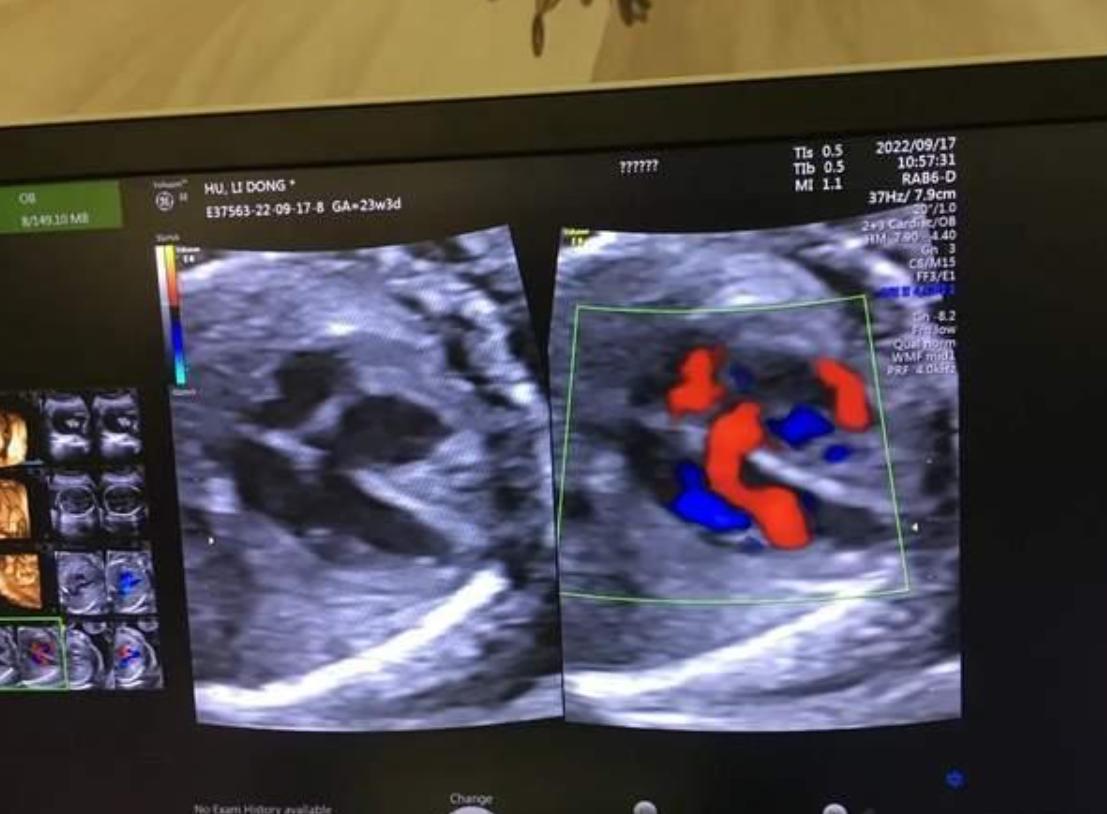

因爲我們做B超的時候,只能看到孩子的心臟有沒有畸形,孩子的五官有沒有畸形?孩子的手有沒有多一個手指或者少一個手指,但是孩子的耳朵聽不聽得到眼睛看不看得到,在B超裏面是沒有辦法去檢測的。

第三個問題:可以篩查出先天的心臟問題

產檢的時候如果發現有先天性的心臟缺陷,這些是在B超的時候能夠看得出來的,並不是100%的全部可以檢出來,但是大部分都能檢出來,當出現嚴重的心臟問題的時候,這些孩子即使出生了也有可能需要家長花費巨資去做心臟的手術。